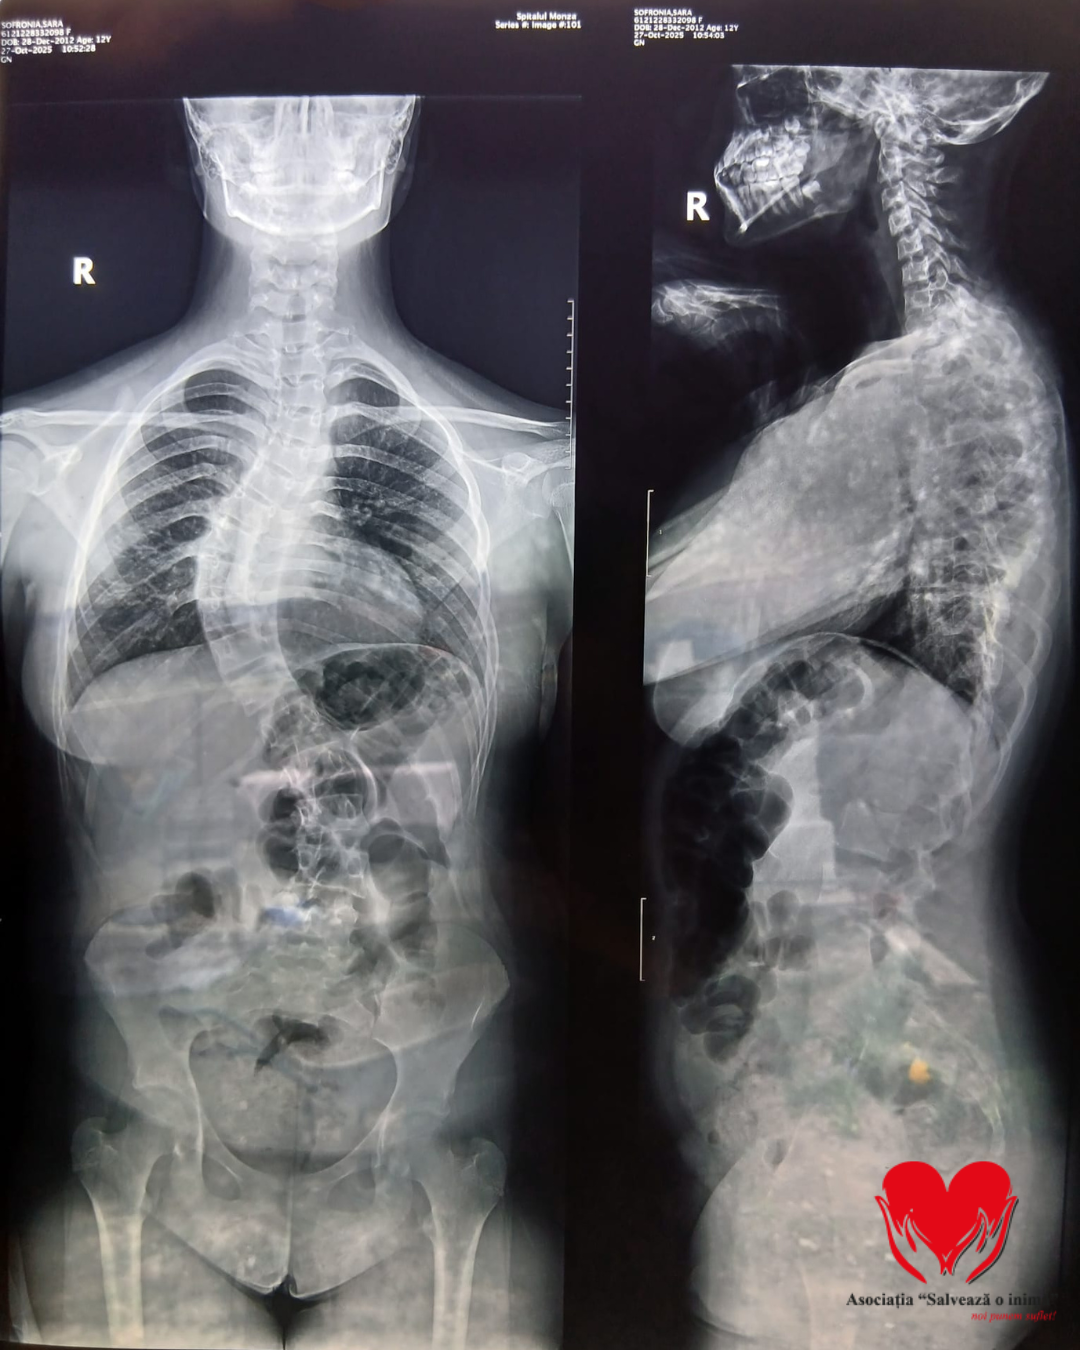

Sara Sofronia, o adolescentă de 13 ani, se confruntă cu o formă severă de scolioză, o afecțiune care îi afectează coloana vertebrală și îi pune în pericol sănătatea. Boala este progresivă și îi influențează atât postura, cât și respirația, reducându-i șansele la o viață normală.

Născută în Italia, alături de sora sa geamănă, Sara s-a întors anul trecut în România împreună cu familia. La scurt timp după revenire, au apărut durerile, iar diagnosticul primit a indicat necesitatea unei intervenții chirurgicale urgente.